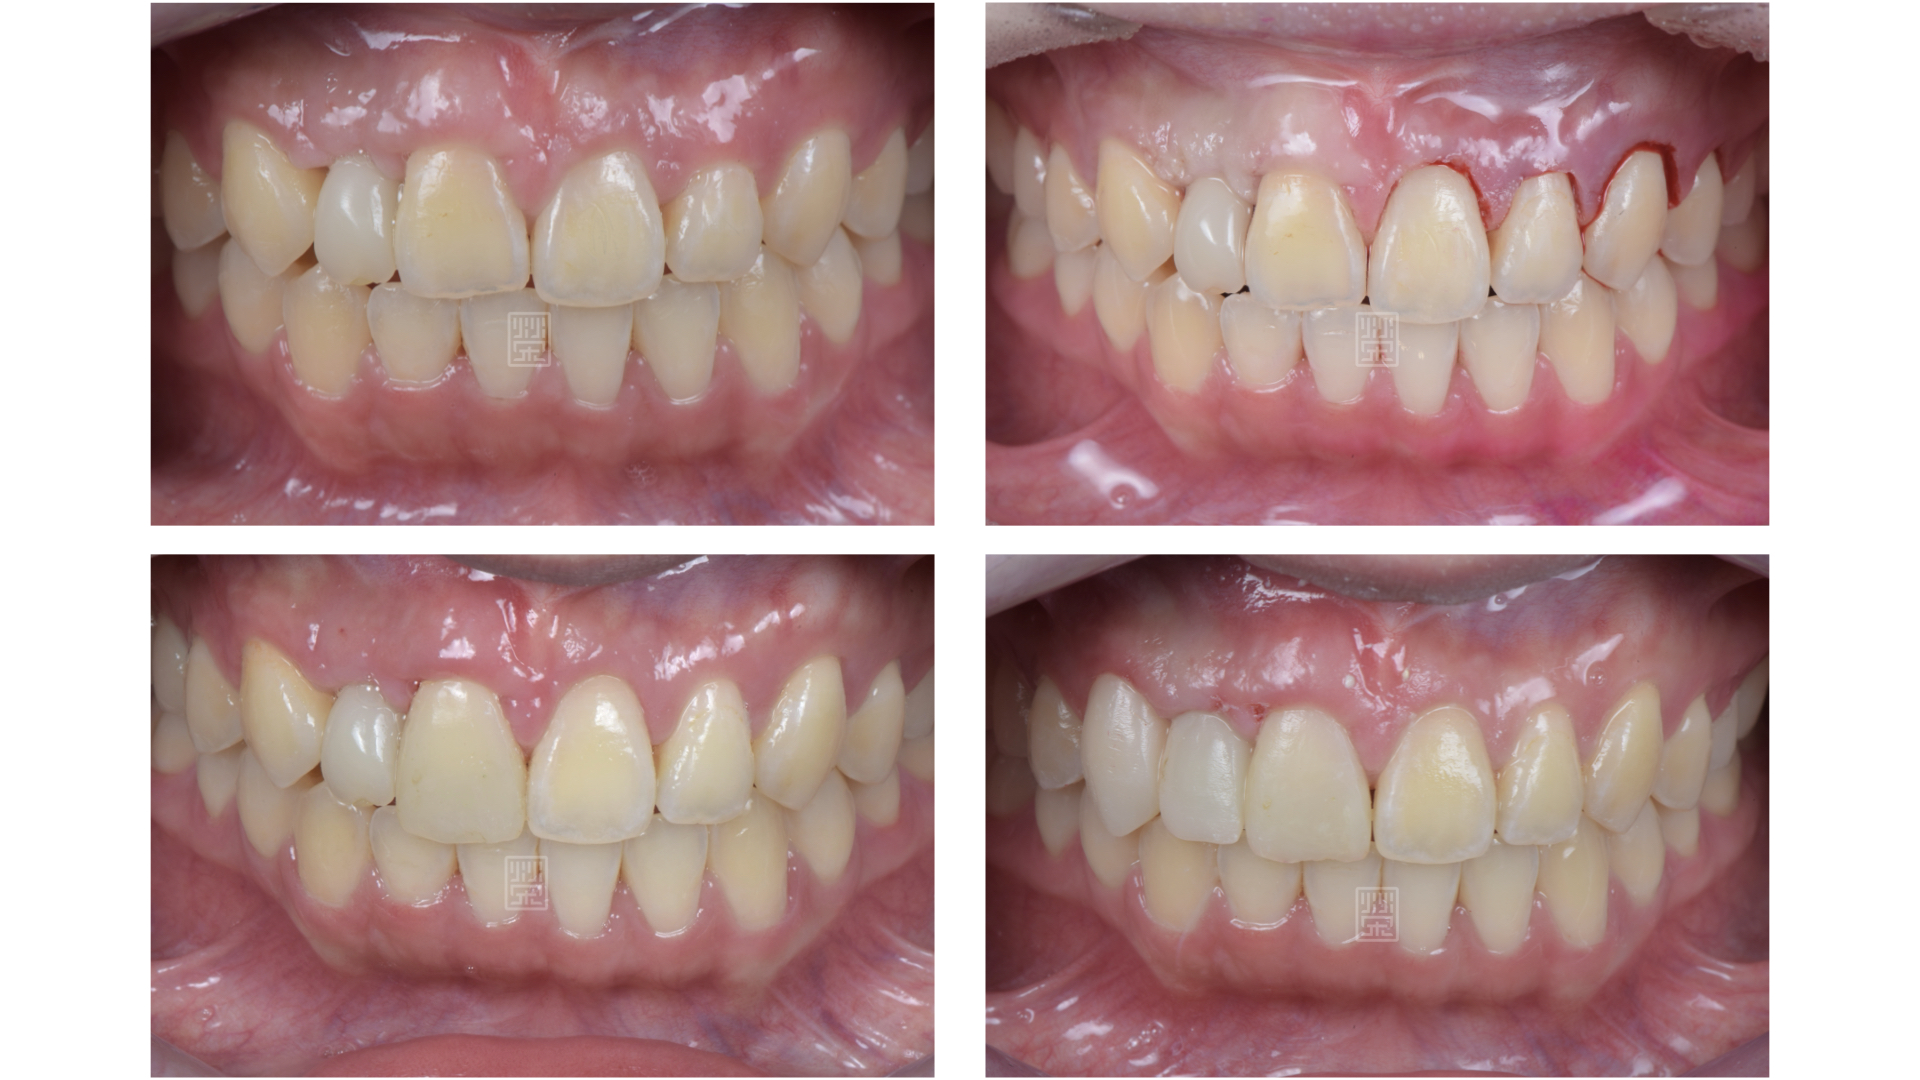

治療前牙齒因車禍有縫且缺牙

矯正移出側門牙空間